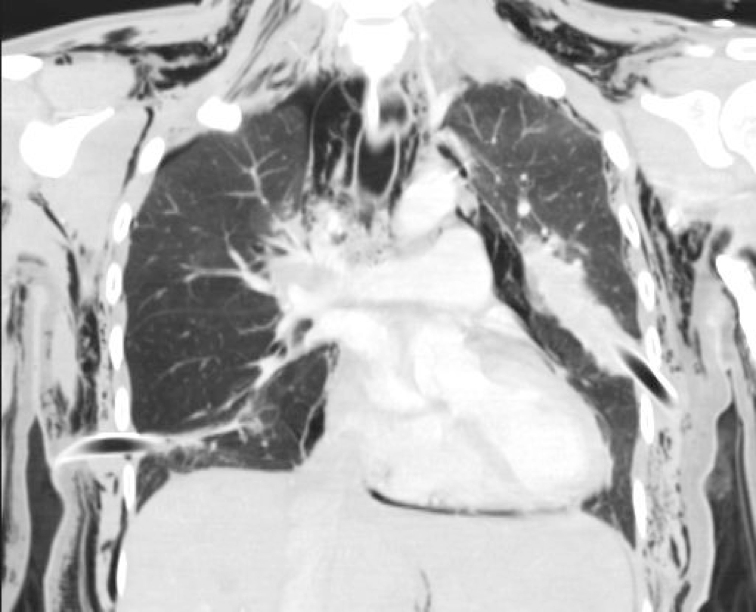

Computed tomography of the cervical spine, chest (Box 2) and abdomen showed injuries involving the spine, ribs, sternum, lungs and liver (Box 3).

2 Coronal computed tomography of the chest showing residual right-side pneumothorax, pneumomediastinum, extensive bilateral subcutaneous emphysema and bilateral intercostal catheters

3 Injuries sustained by the woman and identified by trauma computed tomography

Fractures

- Left C1 transverse process

- Sternum (undisplaced)

- Left ribs: 1, 2–5 (flail segment), 6–8

- Right ribs: 1–2

- Right sternochondral joint angulation: ribs 3–5

Other

- Left haemopneumothorax

- Right pneumothorax and pneumomediastinum

- Bilateral pulmonary contusions

- Extensive bilateral lower lobe collapse

- Periportal oedema of the liver

- Extensive subcutaneous emphysema